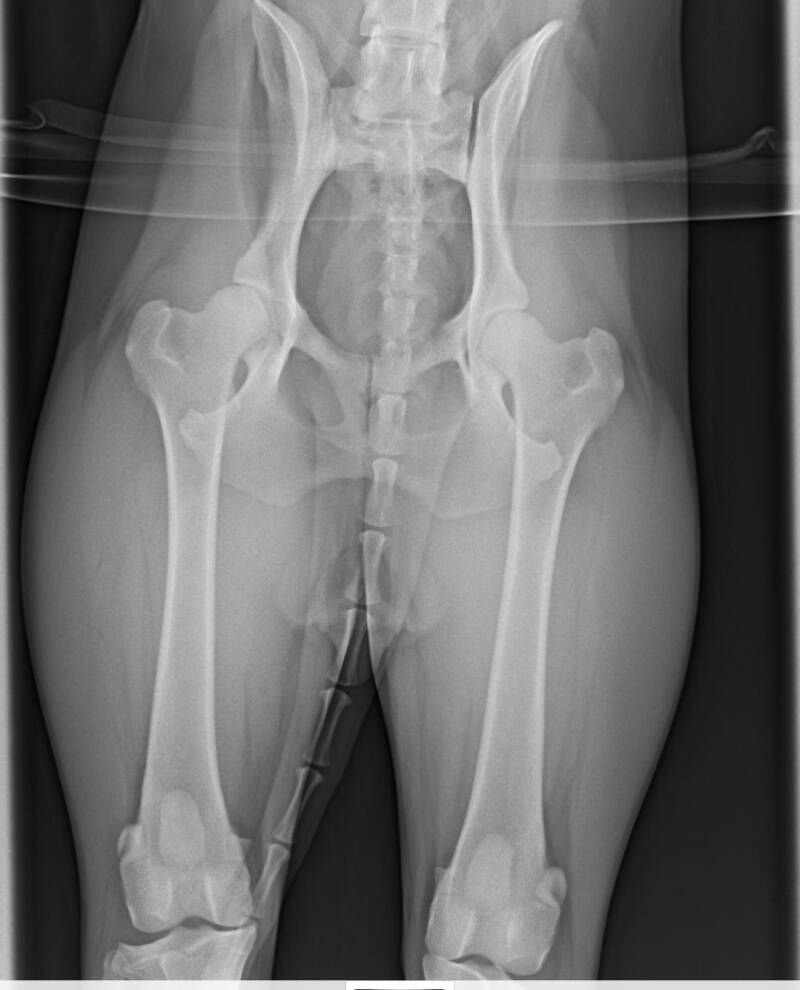

Röntgenfoto:

HD A